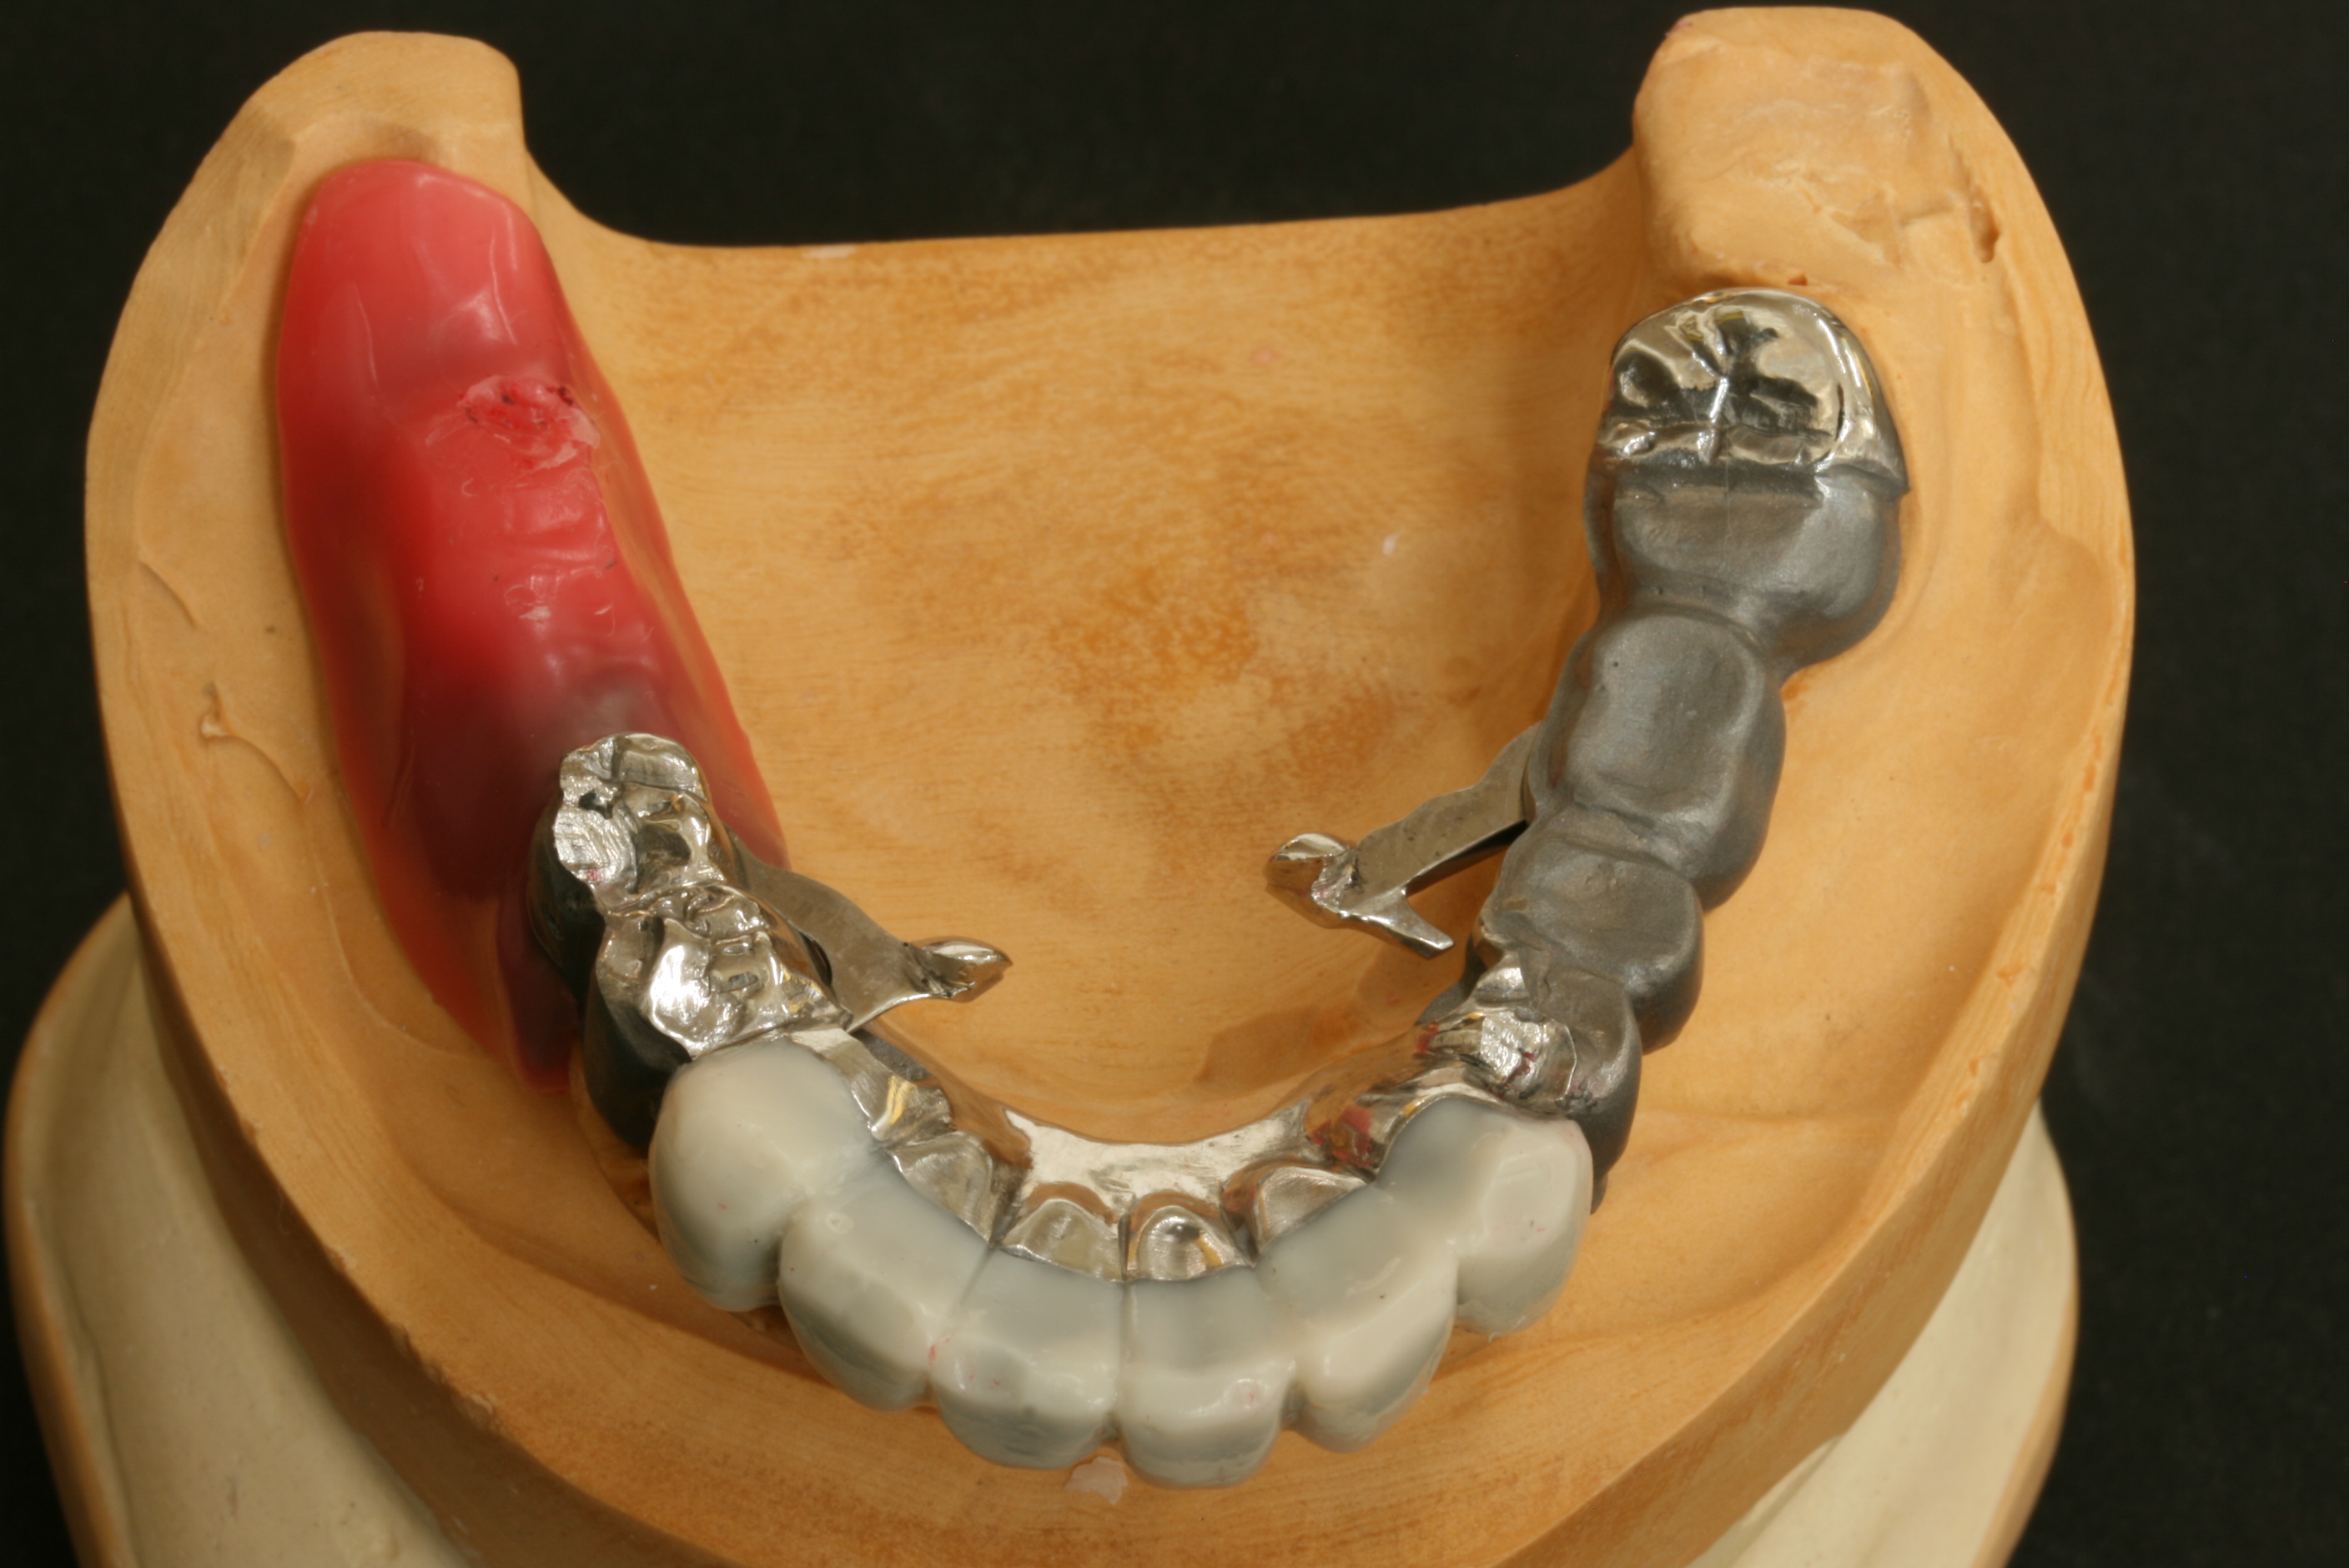

前歯の白い部分は仕上がりをイメージして、ワックスで仮に仕上げてあります。

この入れ歯は、奥歯のほとんどの部分を白く仕上げる予定です。

白い部分は、陶材(ポーセレン)を焼き付けて美しく仕上げる予定です。

テレスコープにおいては、技術的に非常に難しい仕上げ方ですが、順調に試適を終えました。

リーゲルレバー(閂カンヌキ又はスイングロックとも言う)を開いたところです。

外冠を取り外すことができます。